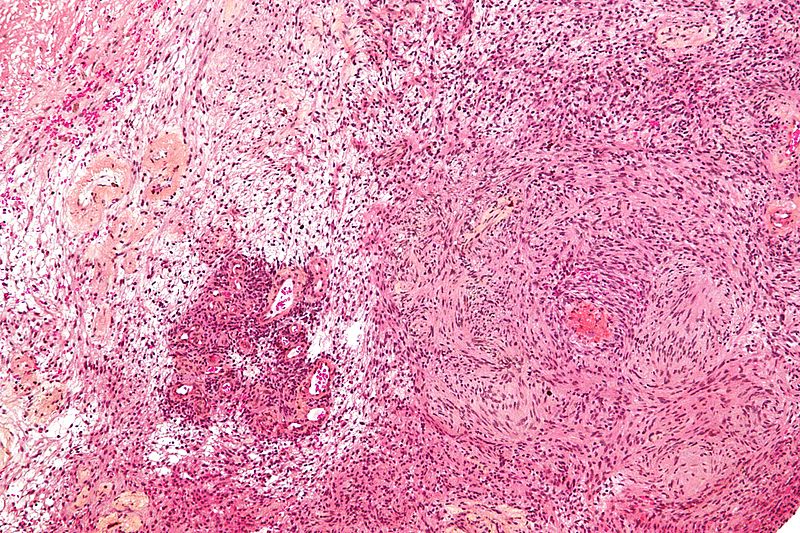

The histology of meningiomas is characterized by a whorled pattern with psammoma bodies.

The histology of schwannomas is characterized by spindle cells that are S-100 stain positive.

Histology of oligodendrogliomas typically show “fried egg” appearing cells that are pathognomonic for this tumor.

Histology of pilocytic astrocytomas shows eosinophilic granular aggregates and Rosenthal fibers (thick eosinophilic processes of the astrocytes).

The histology of medulloblastomas shows small, rounded blue cells are visible on histology, and Homer-Wright rosettes might be present.

Histology of ependymomas classically show perivascular pseudorosettes are seen.